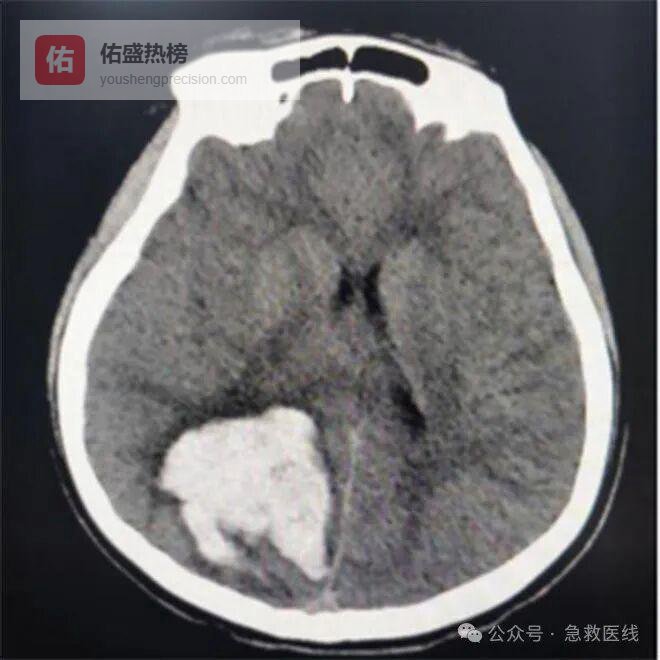

十一、脑出血

(一)诊断

1、发病年龄常在40岁以上,多数有原发性高血压病史。

2、突然起病、常迅速出现头痛、头晕、呕吐和意识障碍,脑局灶性症状因出血部位不同而异。以基底核区(内囊)出血所致的偏瘫、偏身感觉障碍和失语常见,多有血压升高。

3、临床分型:内囊出血、丘脑出血、脑叶出血、脑桥出血、小脑出血、脑室出血。

4、辅助检查:头颅CT扫描可见高密度血肿。